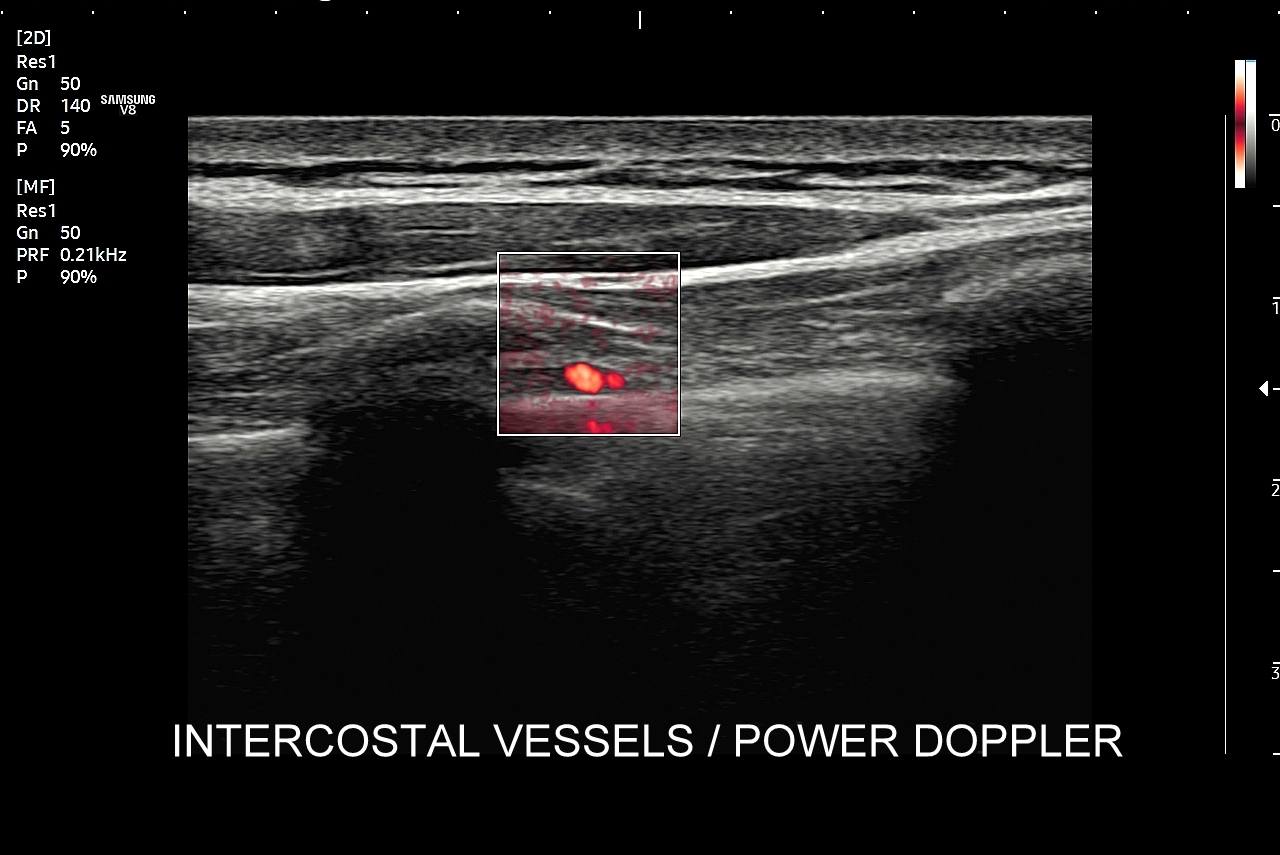

Badanie USG płuc w wybranych przypadkach korzystnie jest połączyć z jednoczesną oceną echokardiograficzną serca oraz dużych naczyń klatki piersiowej, tj. aorty wstępującej i tętnic płucnych. USG układu mięśniowo-szkieletowego klatki piersiowej wykorzystywane jest z kolei w diagnostyce stanów urazowych, takich jak złamanie żeber, czy przeciążenie połączeń chrzęstno-kostnych żeber; w wymienionych przypadkach USG ma wyższą czułość w porównaniu do oceny rentgenowskiej.

Specjalista chorób wewnętrznych. Absolwent Akademii Medycznej we Wrocławiu w 2000 r. Zwolennik nowoczesnych technologii i pionier niestandardowych zastosowań USG w Polsce, w tym użycia obrazowania mikroprzepływów w obrazowaniu płuc, czy badań USG z kontrastem. Na początku lat 2000-ych był jednym z pierwszych lekarzy, który wdrażali szerokie zastosowanie USG w intensywnej terapii. W praktyce ambulatoryjnej wprowadził do regularnego użycia kompleksowe badanie USG klatki piersiowej, płuc i serca. Posiada wieloletni staż kliniczny i szkoleniowy w Polsce oraz zagranicą (Wielka Brytania, Niemcy, Austria, Włochy, Rumunia). Wykonał ponad 40.000 badań USG. Dydaktyk i nauczyciel młodego pokolenia lekarzy w Polsce i Europie.